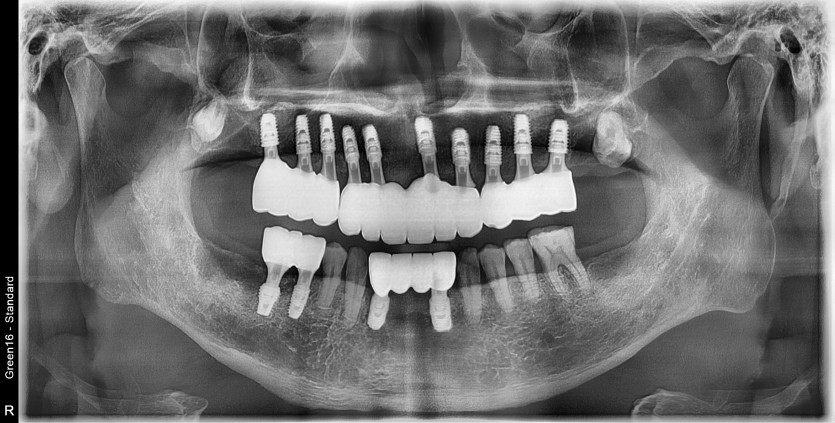

상악 전체 임플란트 증례입니다.(하악 일부)

14개의 임플란트로 완성하였습니다.